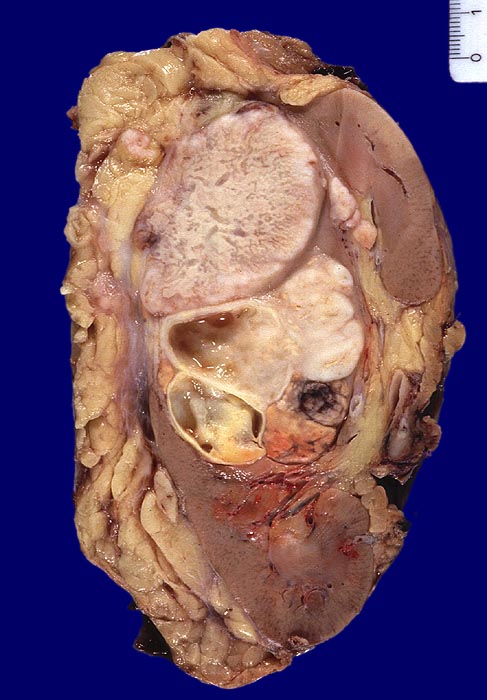

sarkomatoides und teils hellzelliges Nierenzellkarzinom

Im Nierenunterpolbereich und mittleren Abschnitt ein bunter, teils gelber, teils weisser, teils zystischer Tumor Dm 8,2cm. Fokale kleinere Einblutungen. Der Tumor infiltriert das Nierenbeckenfettgewebe und durchbricht auch die Nierenkapsel mit Infiltration des perirenalen Fettgewebes.

Histologie: Überwiegend wenig differenziertes sarkomatoides und teils hellzelliges Nierenzellkarzinom.